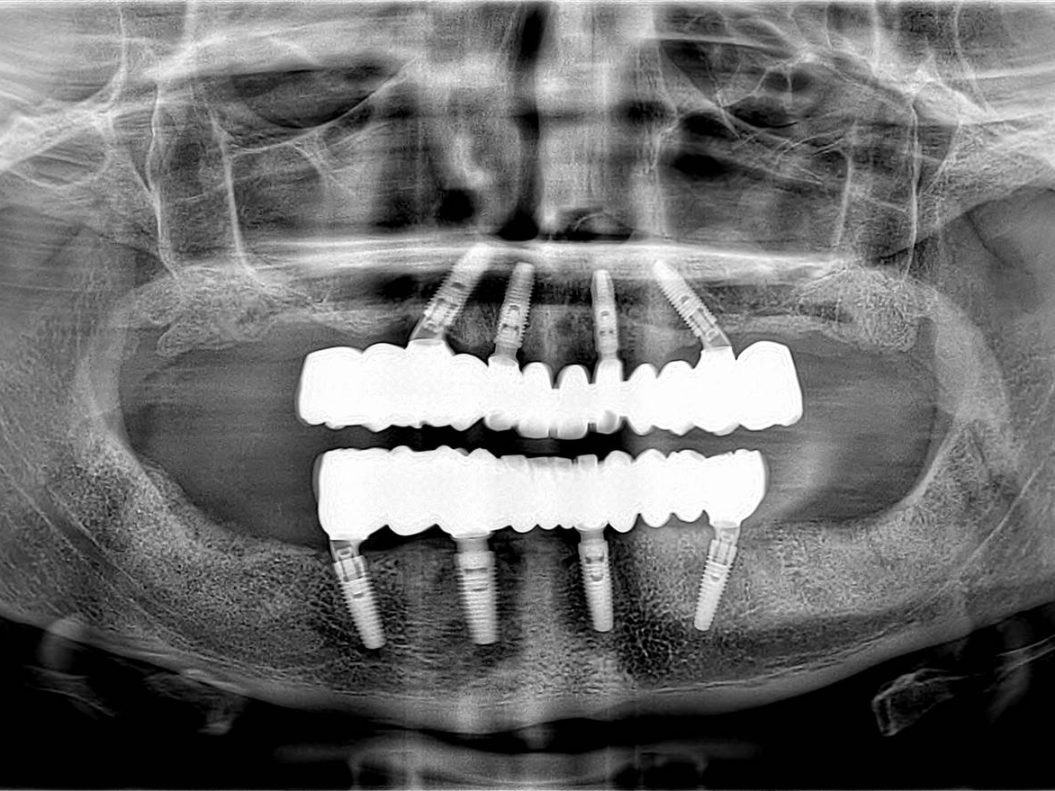

- Radiografia post-operatoria